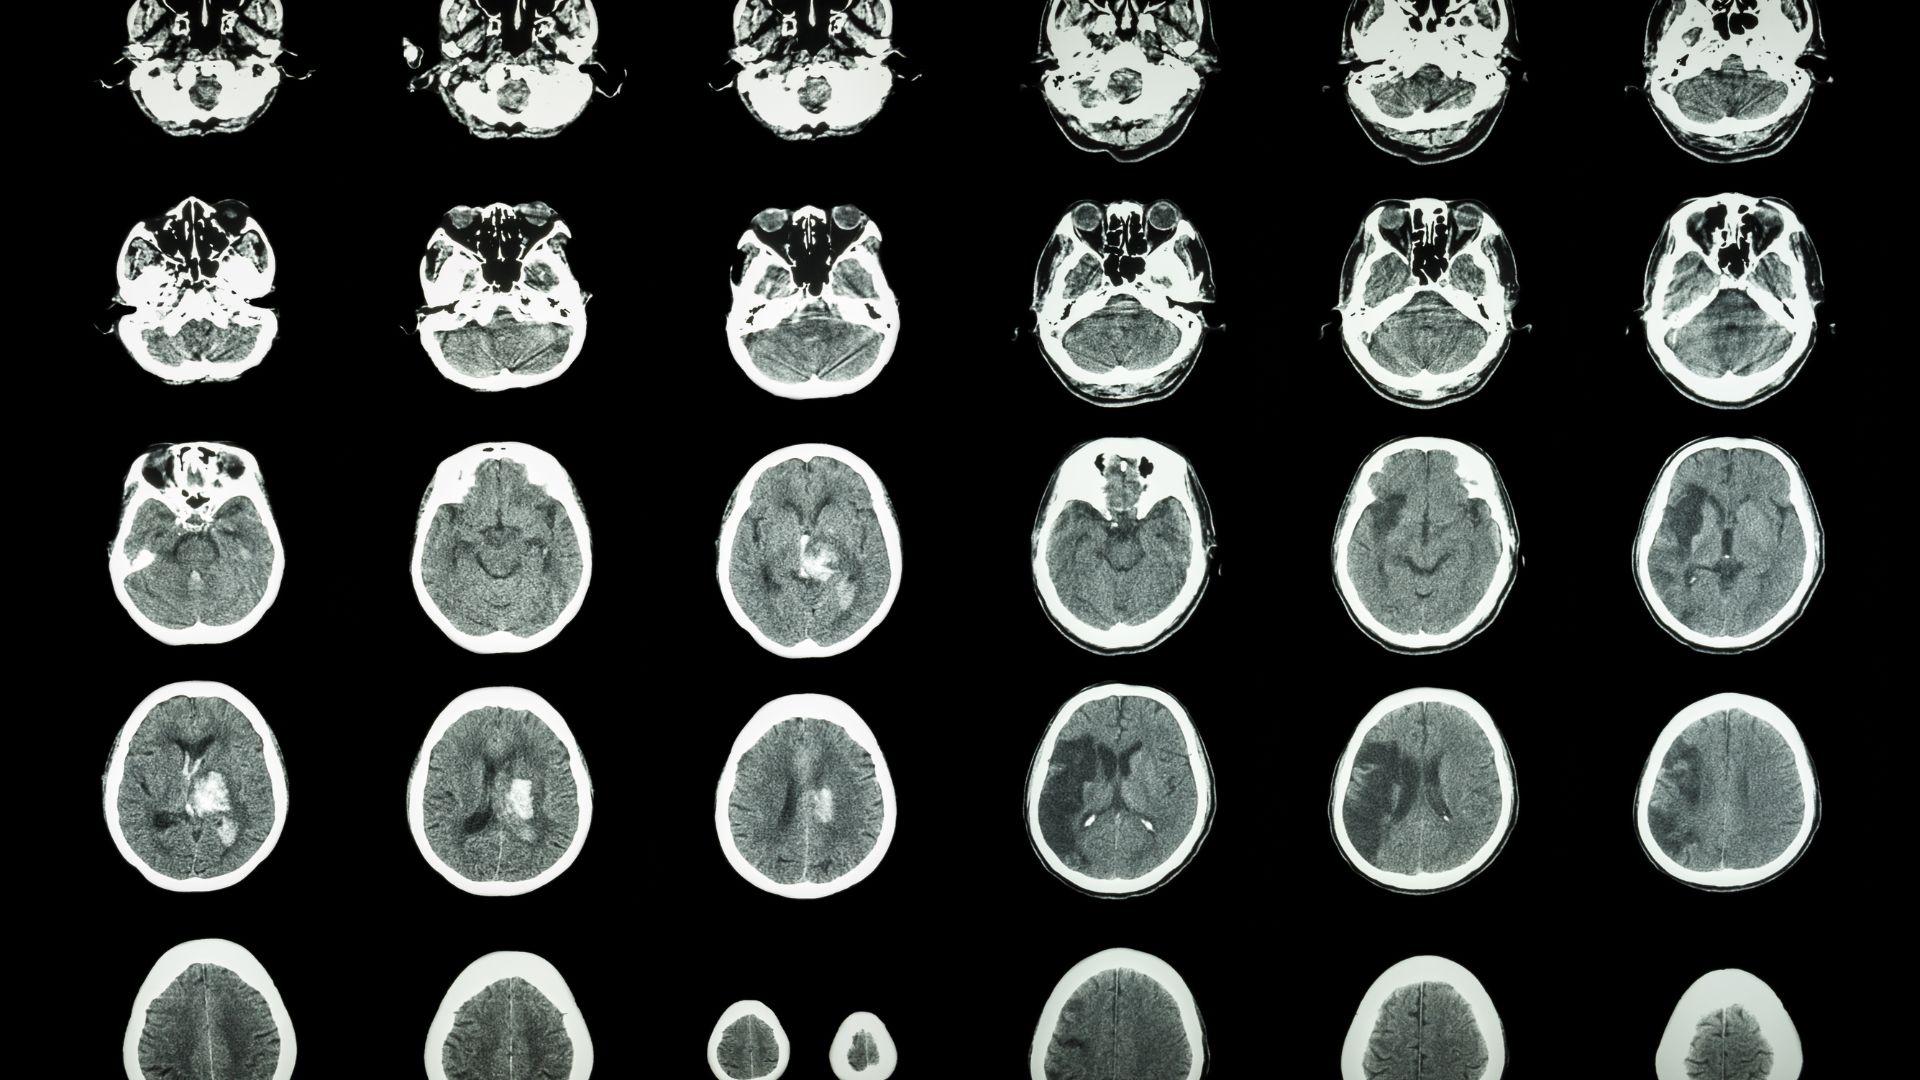

Pacientes com fibrilação atrial têm um risco até cinco vezes maior de sofrer um AVC. Isso acontece porque a arritmia compromete o fluxo sanguíneo normal, facilitando a formação de trombos, especialmente no apêndice atrial esquerdo. Quando um coágulo se desprende e alcança o cérebro, o resultado pode ser um AVC isquêmico grave.